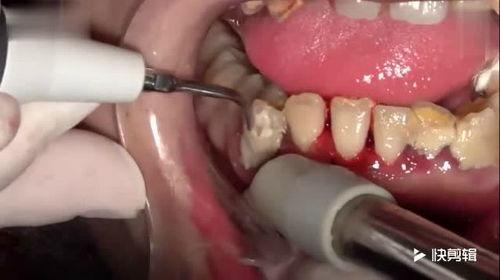

洗牙石的话音刚落,屏幕上立刻出现了一系列搞笑的画面。原来,这块洗牙石见证了无数患者的牙科治疗过程,从拔牙到补牙,从洗牙到镶牙,它都一一记录在案。

接着,视频展示了洗牙石的“朋友圈”。原来,它和牙科诊所里的其他洗牙石、牙科工具们关系密切,它们经常在闲暇时互相交流心得。

“你们看,这是我最近见证的一次拔牙手术,医生的技术真是高超啊!”洗牙石自豪地展示着一张照片。